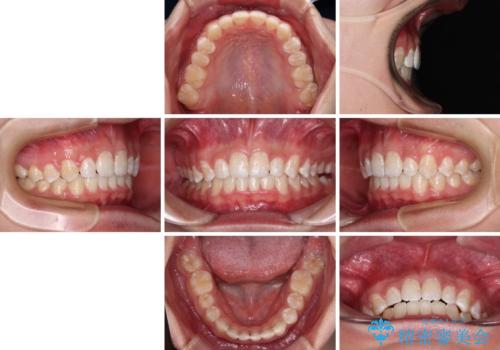

- 強い咬み合わせと前歯のデコボコを気にして来院された患者様です。

下顎前歯が全て隠れてしまうほどの深い咬合で、左右の奥歯は1歯対1歯で咬み合う状態でした。

前方に移動している上顎臼歯を補助装置にて遠心移動させることで1歯対2歯の臼歯咬合を目指し、同時に深い咬合を改善していくこととしました。